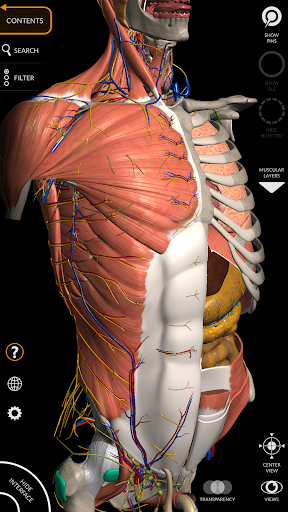

"Anatomía - Atlas 3D" permite estudiar la anatomía humana de forma fácil e interactiva.

A través de una interfaz sencilla e intuitiva es posible observar cada estructura anatómica desde cualquier ángulo.

Los modelos anatómicos 3D son especialmente detallados y con texturas de hasta una resolución de 4k.

MODELOS ANATÓMICOS 3D

• Sistema musculoesquelético

nervioso • Sistema respiratorio • Sistema digestivo • Sistema urogenital (masculino y femenino) • Sistema endocrino • Sistema linfático • Sistema ocular y auditivo CARACTERÍSTICAS • Interfaz sencilla e intuitiva • Rotar y hacer zoom en cada modelo en el espacio 3D • Opción para ocultar o aislar uno o varios modelos seleccionados • Filtro para ocultar o mostrar cada sistema • Función de búsqueda para encontrar fácilmente cada parte anatómica • Función de marcador para guardar vistas personalizadas • Rotación inteligente que mueve el centro de rotación automáticamente • Función de transparencia • Visualización de músculos a través de niveles de capas desde las superficiales hasta las más profundas • Al seleccionar un modelo o un pin, aparece el término anatómico relacionado • Descripción de los músculos: origen, inserción, inervación y acción • Mostrar/ocultar interfaz de usuario (muy útil con pantallas pequeñas) MULTILINGÜE • Los términos anatómicos y la interfaz de usuario están disponibles en 11 idiomas: latín, inglés, francés, alemán, italiano, portugués, turco, ruso, español, Chino, japonés y coreano • Los términos anatómicos se pueden mostrar en dos idiomas simultáneamente REQUISITOS DEL SISTEMA • Android 8.0 o posterior, dispositivos con al menos 3 GB de RAM Reversi